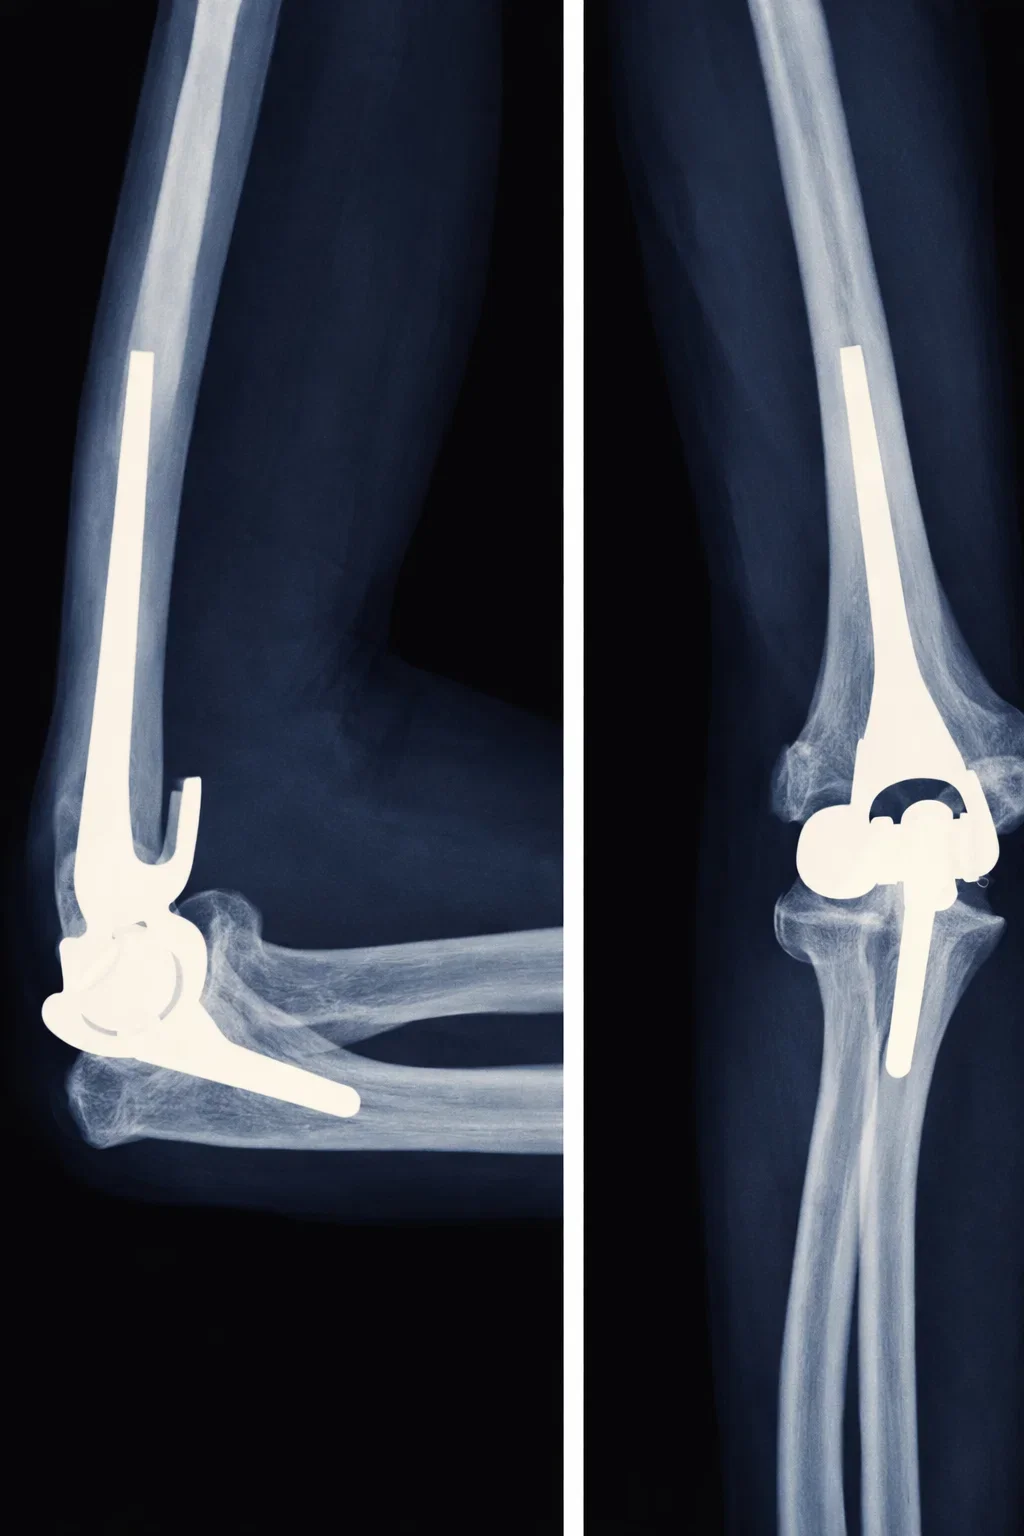

Surgical Procedure

The goal of elbow joint replacement surgery is to eliminate your pain and increase the mobility of your elbow joint. The surgery is performed under sterile conditions in an operating room under general or regional anesthesia and involves the following steps:

• The damaged joint surfaces of the humerus, radius and ulna are cut off with a surgical saw to create a smooth surface to attach the implants.

• A special instrument is used to hollow out the inside of the humerus bone in order to insert the humeral component of the prosthesis.

• Once a proper fit is established, the surgeon repeats this procedure on the ulna bone to prepare it for the ulnar component of the prosthesis.

• The humerus and ulna bones are then prepared with or without cement, depending on the surgeon’s preference.

• The components are then inserted and put together ensuring proper movement of the hinge portion of the prosthesis.

• With all the new components in place, the joint is tested through its range of motion.